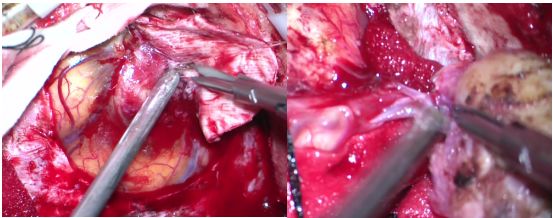

排除手术禁忌后,于05-29在全麻下行“左顶部肿瘤切除术”。术中见肿瘤位于左侧顶部矢状窦旁,与脑膜粘连紧密,血供中等,质地较韧,呈实质性。取少量肿瘤组织送冰冻提示(左顶部矢状窦旁)脑膜瘤。肿瘤予显微镜下全切(图2)。

图2. 术中所见